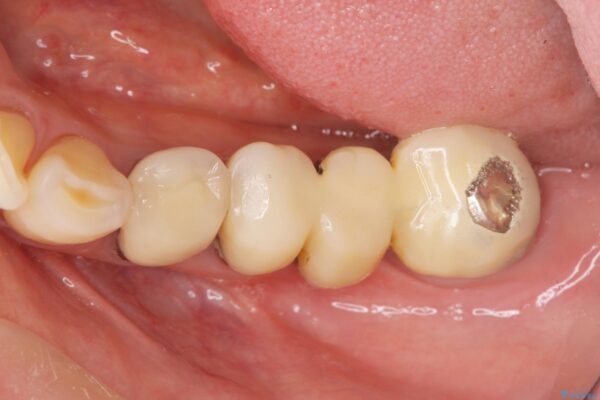

治療前

劣化の進んだブリッジの再治療[ 不適合な補綴物による虫歯の再発 ] 治療前画像 劣化の進んだブリッジの再治療[ 不適合な補綴物による虫歯の再発 ] 治療前画像 劣化の進んだブリッジの再治療[ 不適合な補綴物による虫歯の再発 ] 治療前画像